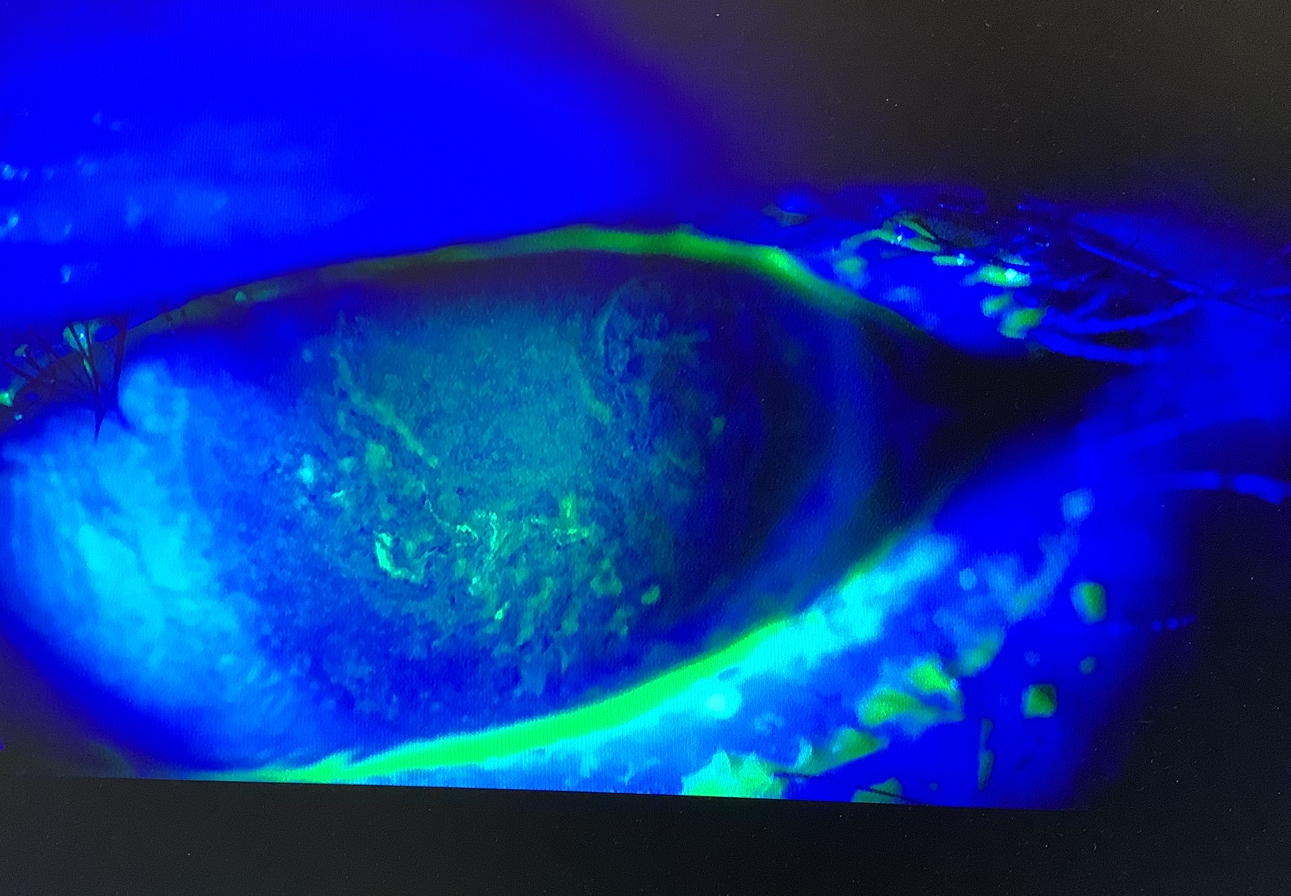

今日の外来では、加齢黄斑変性で抗VEGF薬の硝子体注射を繰り返している70代の半ばの男性の方の経過観察がありました。この方は、歯科の先生なのですが、2021年頃から当院に通ってくださり、硝子体注射を左右で合計27回行っていますが、8月の下旬に左眼の注射を行った後から角膜のキズができて視力が低下し、点眼と軟膏を処方して経過を見ているところでした。少しずつよくはなっているのですが、結構、重度の角膜障害だったので、改善に時間がかかってしまい、『私は高齢だけれど、現役で仕事もしていて、見えなくなってしまうと困るんだ』とおっしゃっていました。もちろん、この患者さんのお仕事も知っていますし、職業上、眼が大事なことも分かった上で、少しでも早くよくなるように、少しでも後遺症が出ないように治療をしています。ただ、それは患者さんの職業や仕事をしているか、リタイアしているかは関係ありません。どんな人でも見え方が悪くなれば、困ることに変わりはないですし、どんな人でも少しでもよくなるように治療をしているつもりです。白内障の手術の時のレンズの選択などでは、どんな仕事をしているかが、大切な要素になることはありますが、職業で治療の力の入れ方を変えることはありません。それよりも、仕事が忙しくて点眼を十分につけていなかったり、軟膏を入れると余計に見えなくて仕事に差し支えがあるということで使っていなかったり、僕の指示をきちんと守っていただけていなかったので、見えなくなってしまって困るなら、点眼や軟膏をきちんと使う努力をしていただくように話させていただきました。少しでも早くちゃんとよくなるように考えて診療をしていますので、患者さんの側でも事情はあるのは分かりますが、できる範囲でご理解、ご協力、よろしくお願いいたします。